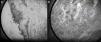

Patient 2. The patient was a 92-year-old woman with hypertension under treatment with chlortalidone/spironolactone who began to develop telangiectasias on both lower limbs at the age of 50 years (Fig. 2). The lesions were asymptomatic and gradually descended to the dorsum of the feet and soles. The telangiectasias were initially red in color (Fig. 3A) but became darker over time until they took on a violaceous tone, leaving hyperkeratotic lesions and microvarices (Fig. 3B). Dermoscopy of the oldest lesions revealed vascular dilations with a tortuous, serpentine pattern (Fig. 3B inset). The results of additional tests (complete blood count, coagulation tests, biochemistry, and screening for antinuclear antibody, anti–extractable nuclear antigen antibody, rheumatoid factor, hepatitis C virus, and cryoglobulins) were normal. Two skin biopsy samples were taken for routine histology, and another specimen was taken for electron microscopy. Histology of the red telangiectasias (proximal third of the leg) revealed dilated vessels in the papillary dermis with slight wall thickening. The vessels were surrounded by an amorphous eosinophilic material that stained with Masson trichrome and periodic acid–Schiff (PAS) diastase. Immunohistochemistry was positive for collagen IV, with reduplication of the basement membrane in the form of concentric layers (Fig. 4). Electron microscopy revealed reduplication and focal disruption of the basement membrane accompanied by deposition of collagen fibers with an anomalous pattern (Fig. 5). These histopathology findings are diagnostic of CCV.

Histology study for Patient 2 (cutaneous collagenous vasculopathy). A, Vessels with slightly thickened walls in the upper dermis (hematoxylin-eosin, original magnification, ×20). B, Perivascular deposition of material that stained with periodic acid–Schiff diastase (×40). C, Immunohistochemistry revealed strongly positive results for collagen IV, thus indicating reduplication of the basement membrane (×40).